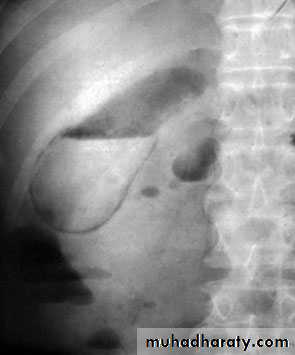

Cholecystitis. Ultrasound demonstrates pericholecysticfluid (thin arrow), gall bladder wall (thick arrow) and biliary sludge

Gas in the gall bladder and gall bladder wall(Clostridium perfringens). Emergency surgery is indicated.